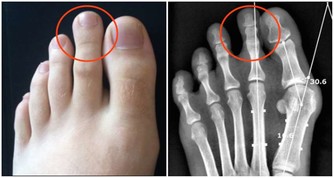

3.血栓45-55歲很容易出現血栓、腦血栓、肺栓塞、心梗等,

抽煙、高血壓、糖尿病、高血脂、久坐不動等都是患血栓的高危因素。

血栓雖然不像癌症那樣症狀比較明顯,但是依然會有一些異樣,

比如,很多腿部靜脈血栓患者前期都會出現“腿疼”,腦血栓患者普遍反映會出現頭痛、偏頭痛等。